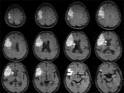

Die Netzhaut: ein Fenster zu Herz und Gehirn: Mit digitaler Fotografie gibt die Netzhaut unseres Auges Aufschluss über den Zustand unserer Herzkranz- und Hirngefäße, denn auch die Netzhautgefäße verändern sich bei Bluthochdruck, sie werden enger und zeigen Gefässwandveränderungen. Diese Veränderungen kann man mit einer "Fundus-Kamera" (Augenhintergrundkamera) fotografieren und einer entsprechenden Auswertung zuführen. Die Verlaufskontrolle zeigt Gefässveränderungen auf. Auf diese Weise erhalten die Patienten sehr schnell einen Hinweis darauf, ob ihre Gefäße bedeutsame "arteriosklerotische" Veränderungen aufweisen.

Durch das Auge zum Gehirn: Mit einer einfachen Untersuchung können wir Augenärzte das Schlaganfall-Risiko unserer Patienten entdecken. Deutsche Mediziner und Techniker des Frauenhofer-Institut für Biomedizinische Technik in München haben dieses neues Aufgabenfeld für Augenärzte entdeckt. Die einfache und ungefährliche Untersuchungsmethode der "Kontaktglas-Dynamometrie" zeigt dem Augenarzt, ob ein Schlaganfall droht: Die Blutgefäße des Augenhintergrunds können untersucht und gleichzeitig der Blutdruck im Auge gemessen werden, denn Bluthochdruckerkrankung (16 Mio. Betroffene in Deutschland) ist der häufigste Risikofaktor für einen Schlaganfall. In der Netzhaut des Auges liegen zahlreiche Blutgefäße, die als Einziger der Augenarzt direkt sehen und so auf krankhafte Veränderungen hin untersuchen kann. Mit der "Kontaktglas-Dynamometrie" kann nun zusätzlich der Blutdruck der Gefäße im Auge hochpräzise gemessen werden. Statt des Stethoskopes, wie bei der Blutdruckmessung am Arm, dient das spezielle "Kontaktglas" mit einem hochempfindlichen Drucksensor der Anzeige des "Pulsierens". Presseberichte: --> Bild am Sonntag [129 KB]

So funktioniert es: die Bestimmung des systolischen und diastolischen Blutdrucks der Zentralarterie des Auges am Sehnervenkopf lässt Rückschlüsse auf den Blutdruck in der "Arteria ophthalmica" an der Abgangsstelle der "Arteria centralis retinae", der einzigen Augenarterie, auf den Blutdruck in der "Arteria carotis interna" und auf den systemischen Blutdruck zu. Diagnostische Bedeutung hatte die Ophthalmodynamometrie bisher vor allem bei Vorliegen haemodynamisch wirksamer ACI-Stenosen (Hirn-Schlagaderverengung). Das "Kontaktglas-Dynamometer" im Vergleich zum älteren "Federdynamometer" bietet jetzt die Möglichkeit, eine präzise Blutdruckmessung im Auge schmerzlos und rasch durchzuführen. Die Bestimmung des Zentralvenendrucks ist bedeutsam bei Venenast - oder Zentralvenenverschlüssen sowie arterio-venösen Fisteln des Sinus cavernosus (einer lebensbedrohlichen Erkrankung). Gefäßverschlüsse im Auge entsprechen dem Schlaganfall im Gehirn. -> mehr zum Prinzip